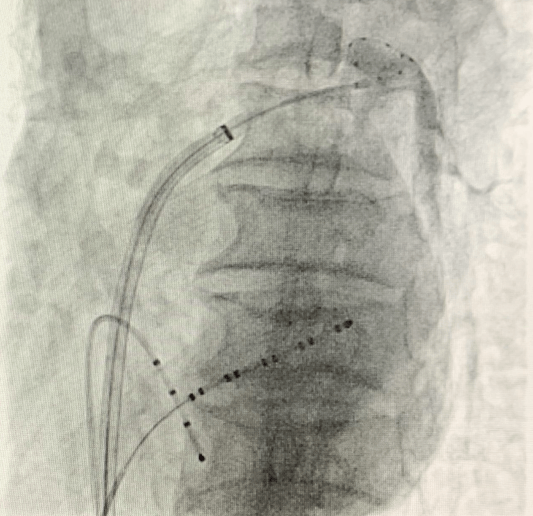

(手術過程)